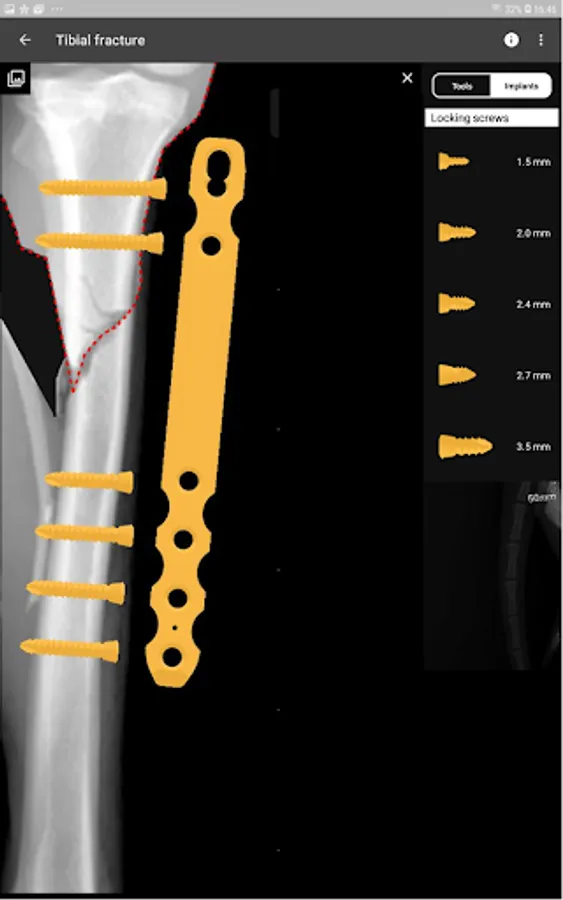

4. Catalogue of BETA Implants locking plates, in 2.0, 2.4, 2.7 and 3.5 sizes:

a) Multi-hole plates

b) Bridge plates

c) Distal radius plates

d) Diaphyseal femur plates

e) T plates

f) Ilium plates

g) Acetabular plates

h) Dorsal pancarpal arthodesis plates

i) Medial pancarpal arthodesis plates

j) Pantarsal arthodesis plates

k) Partial tarsal arthodesis plates

l) CTWO plates

m) TPLO plates

n) Maxilofacial plates

o) Locking screws